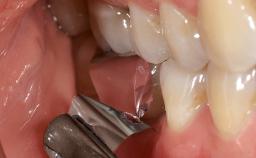

A 30-year-old patient presented at our clinic with a chief complaint of pain in her endodontically treated right maxillary central incisor (tooth 11) with a post-and-core and a fixed single crown. She had a very high lip line, a medium to thin soft-tissue phenotype, and a medium scalloped gingival contour. She also had high esthetic expectations because of her young age and beautiful smile. However, her expectations were realistic and she understood the risks of the treatment. At the initial clinical examination there was a slight mobility of tooth 11; no fistula was observed. The patient also had a single crown on the adjacent tooth 21. Both restorations were old and esthetically deficient. A digital periapical radiograph showed a very small periapical radiolucency, a thick intraradicular post, and no separation between root fragments.